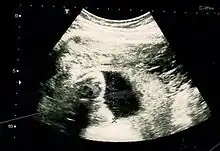

Fetus at 17 weeks

Fetal assessments

Obstetric ultrasonography is routinely used for dating the gestational age of a pregnancy from the size of the fetus, determine the number of fetuses and placentae, evaluate for an ectopic pregnancy and first trimester bleeding, the most accurate dating being in first trimester before the growth of the foetus has been significantly influenced by other factors.[22] Ultrasound is also used for detecting congenital anomalies (or other foetal anomalies) and determining the biophysical profiles (BPP), which are generally easier to detect in the second trimester when the foetal structures are larger and more developed.[23]

X-rays and computerized tomography (CT) are not used, especially in the first trimester, due to the ionizing radiation, which has teratogenic effects on the foetus.[24] No effects of magnetic resonance imaging (MRI) on the foetus have been demonstrated,[25] but this technique is too expensive for routine observation. Instead, obstetric ultrasonography is the imaging method of choice in the first trimester and throughout the pregnancy, because it emits no radiation, is portable, and allows for realtime imaging.[26]

The safety of frequent ultrasound scanning has not been confirmed. Despite this, increasing numbers of women are choosing to have additional scans for no medical purpose, such as gender scans, 3D and 4D scans.[27] A normal gestation would reveal a gestational sac, yolk sac, and fetal pole.[28]

The gestational age can be assessed by evaluating the mean gestational sac diameter (MGD) before week 6, and the crown-rump length after week 6. Multiple gestation is evaluated by the number of placentae and amniotic sacs present.[29]